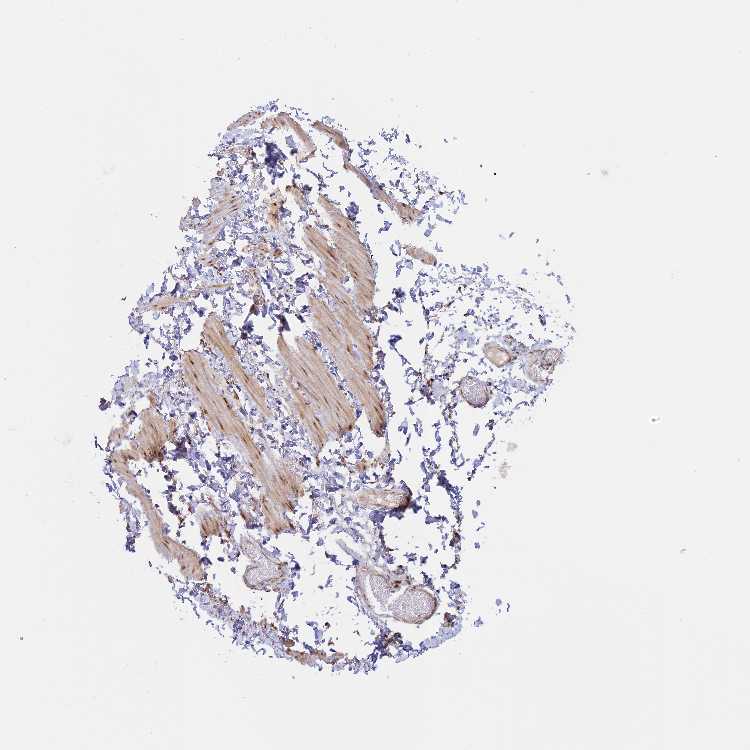

TISSUE PRIMARY DATA SOFT TISSUE Show tissue menu

SOFT TISSUE - Expression summary

SOFT TISSUE 1 - Antibody stainingi

Antibody staining in the annotated cell types in the current human tissue is reported as not detected, low, medium, or high, based on conventional immunohistochemistry profiling in selected tissues. This score is based on the combination of the staining intensity and fraction of stained cells.

Each image is clickable and will lead to virtual microscopy that enables deeper exploration of all samples and also displays staining intensity scores, fraction scores and subcellular localization as well as patient and tissue information for each sample.

Antibody HPA039809Antibody HPA040044

Fibroblasts MediumMedium

Peripheral nerve Not detectedLow